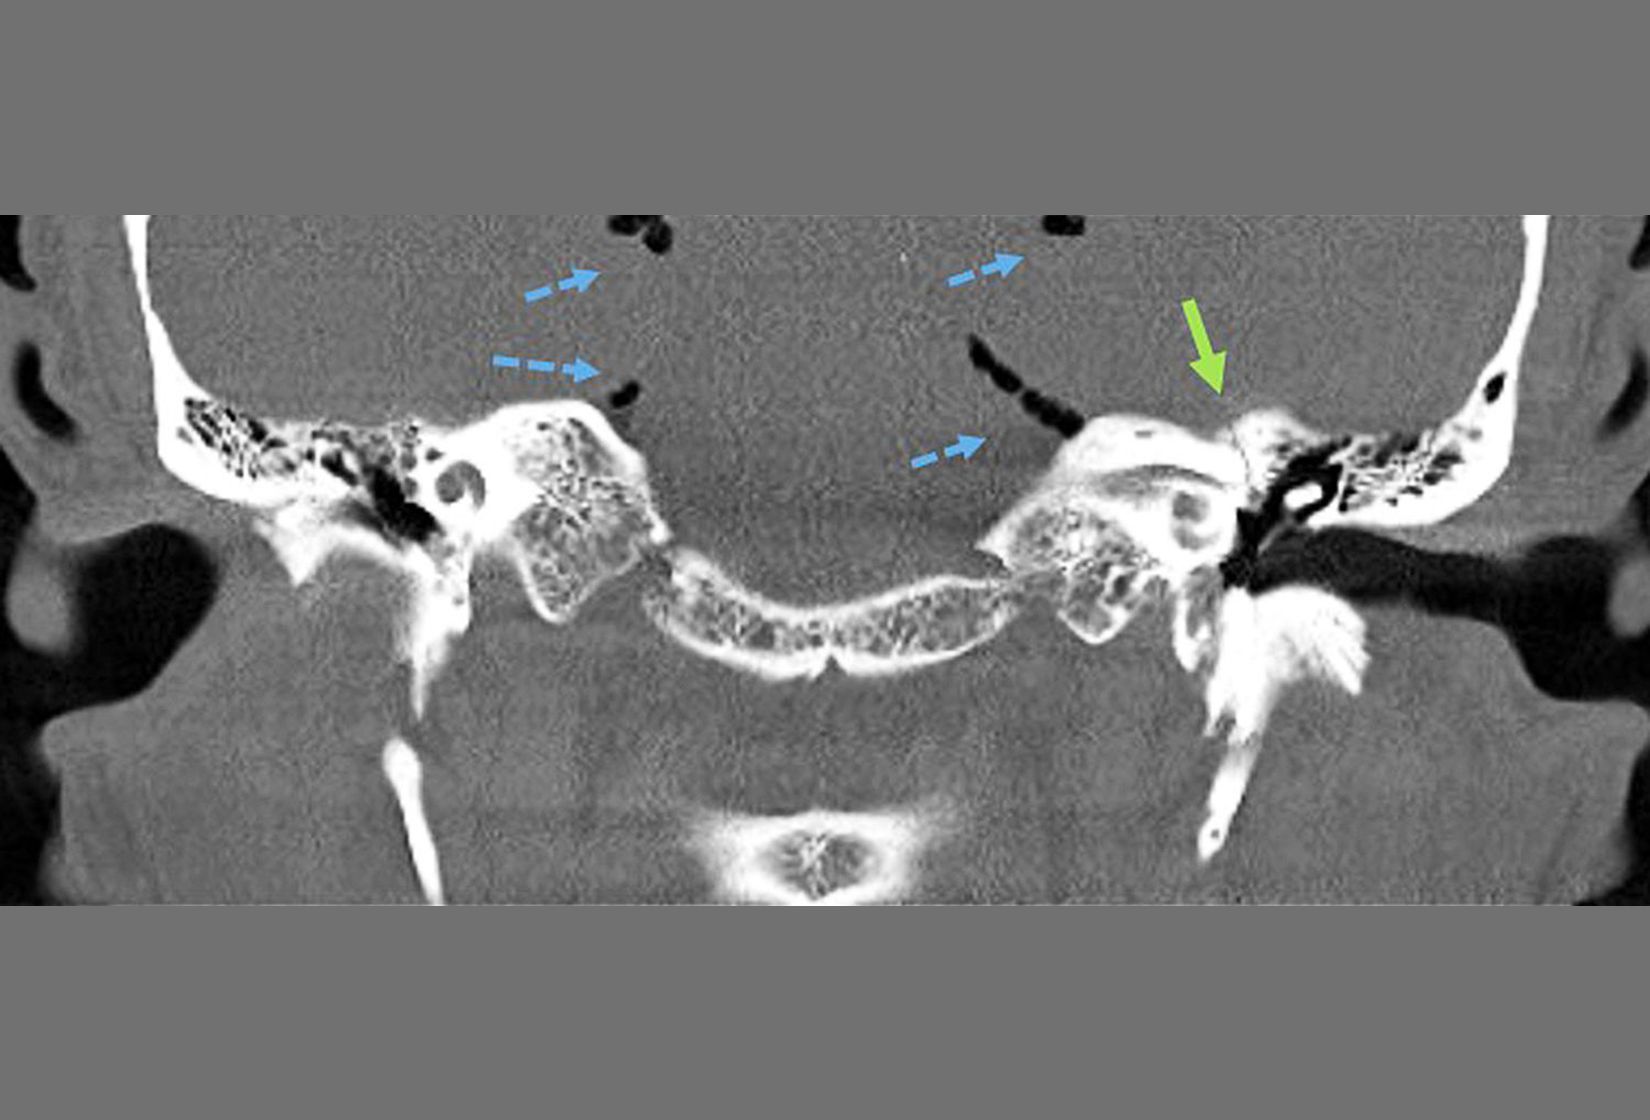

Die Computertomographie (CT) ist ein röntgenologisches Schnittbildverfahren: Ein fächerförmiger Röntgenstrahl dreht sich um den Patienten und wird durch den Körper geschickt. Die hinter dem Patienten austretenden Röntgenstrahlen werden durch ein Messgerät (Detektor) erfasst. Aus einer sehr großen Anzahl von Messwerten berechnet der Computer dünne Querschnittsbilder, die die Dichteverteilung im Körper widerspiegeln.

Die Computertomographie ist eines der wichtigsten Verfahren zur Darstellung von Krankheiten. Nahezu alle Körperregionen können untersucht werden. Häufig sind Untersuchungen des Gehirns, der inneren Organe, des Skeletts und der Blutgefäße. Spezielle CT-Untersuchungen erlauben z.B. die Darstellung der Hirndurchblutung.